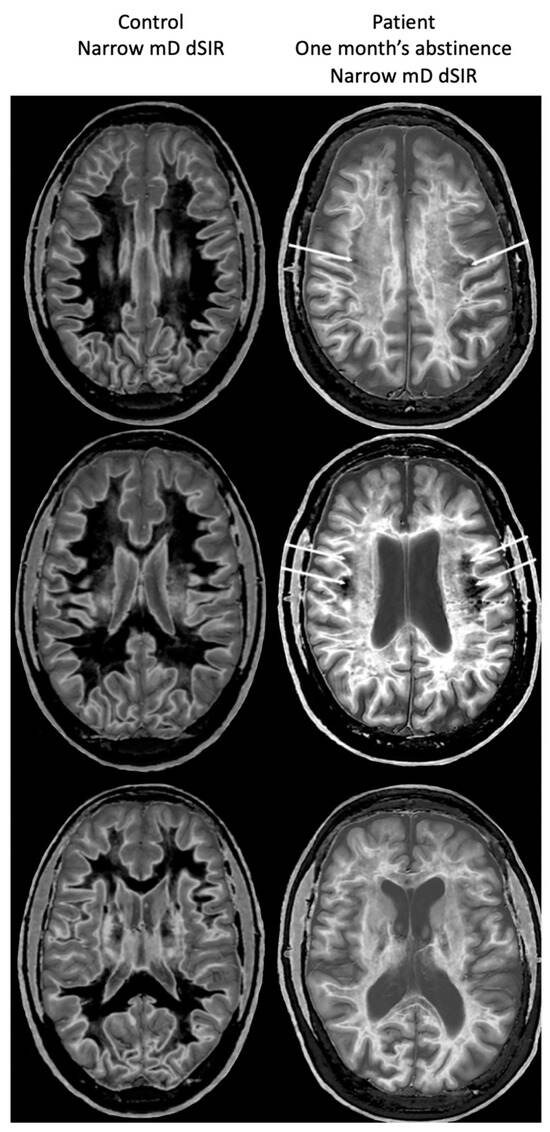

Figure 19 shows narrow mD dSIR images in the patient after one month’s abstinence (left column) and after nine months’ abstinence (right column). Extensive abnormal high signal is seen in white matter after one month’s abstinence (left column). There is marked reduction in the extent of these high signal abnormalities in white matter after nine months abstinence from whiteout sign grade 4 to grade 2 (right column). The patient clinically improved during this period.

Figure 19.

Case 1 patient with methamphetamine use disorder. Comparison of narrow mD dSIR images after one month’s abstinence (left column) and after nine months’ abstinence (right column). After one month’s abstinence the images show widespread abnormal areas of increased signal in white matter (left column). After nine months abstinence, the images show extensive dark low signal areas (right column) consistent with marked regression of his disease during the period between one and nine months’ abstinence from whiteout sign grade 4 (right column) to grade 2 (left column). The boundaries between white and gray matter as well as between CSF and white matter around the lateral ventricles become more obvious after regression of the whiteout sign.